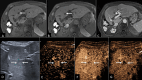

Methods: A prospective international multicenter validation study for CEUS Liver Imaging Reporting and Data System (LI-RADS) was conducted between January 2018 and August 2021. 646 patients at risk for HCC with focal liver lesions were enrolled. CEUS was performed using an intravenous ultrasound contrast agent within 4 weeks of CT/MRI. Liver nodules were categorized based on LI-RADS (LR) criteria. Histology or one-year follow-up CT/MRI imaging results were used as the reference standard. The diagnostic performance of CEUS was evaluated for inconclusive CT/MRI scan in two scenarios for which the AASLD recommends repeat imaging or imaging follow-up: observations deemed non-characterizable (LR-NC) or with indeterminate probability of malignancy (LR-3).

Results: 75 observations on CT or MRI were categorized as LR-3 (n = 54) or LR-NC (n = 21) CEUS recategorization of such observations into a different LR category (namely, into one among LR-1, LR-2, LR-5, LR-M, or LR-TIV) resulted in management recommendation changes in 33.3% (25/75) and in all but one (96.0%, 24/25) observation, the new management recommendations were correct.

Conclusion: CEUS LI-RADS resulted in management recommendations change in substantial number of liver observations with initial indeterminate CT/MRI characterization, identifying both non-malignant lesions and HCC, potentially accelerating the diagnostic process and alleviating the need for biopsy or follow-up imaging.